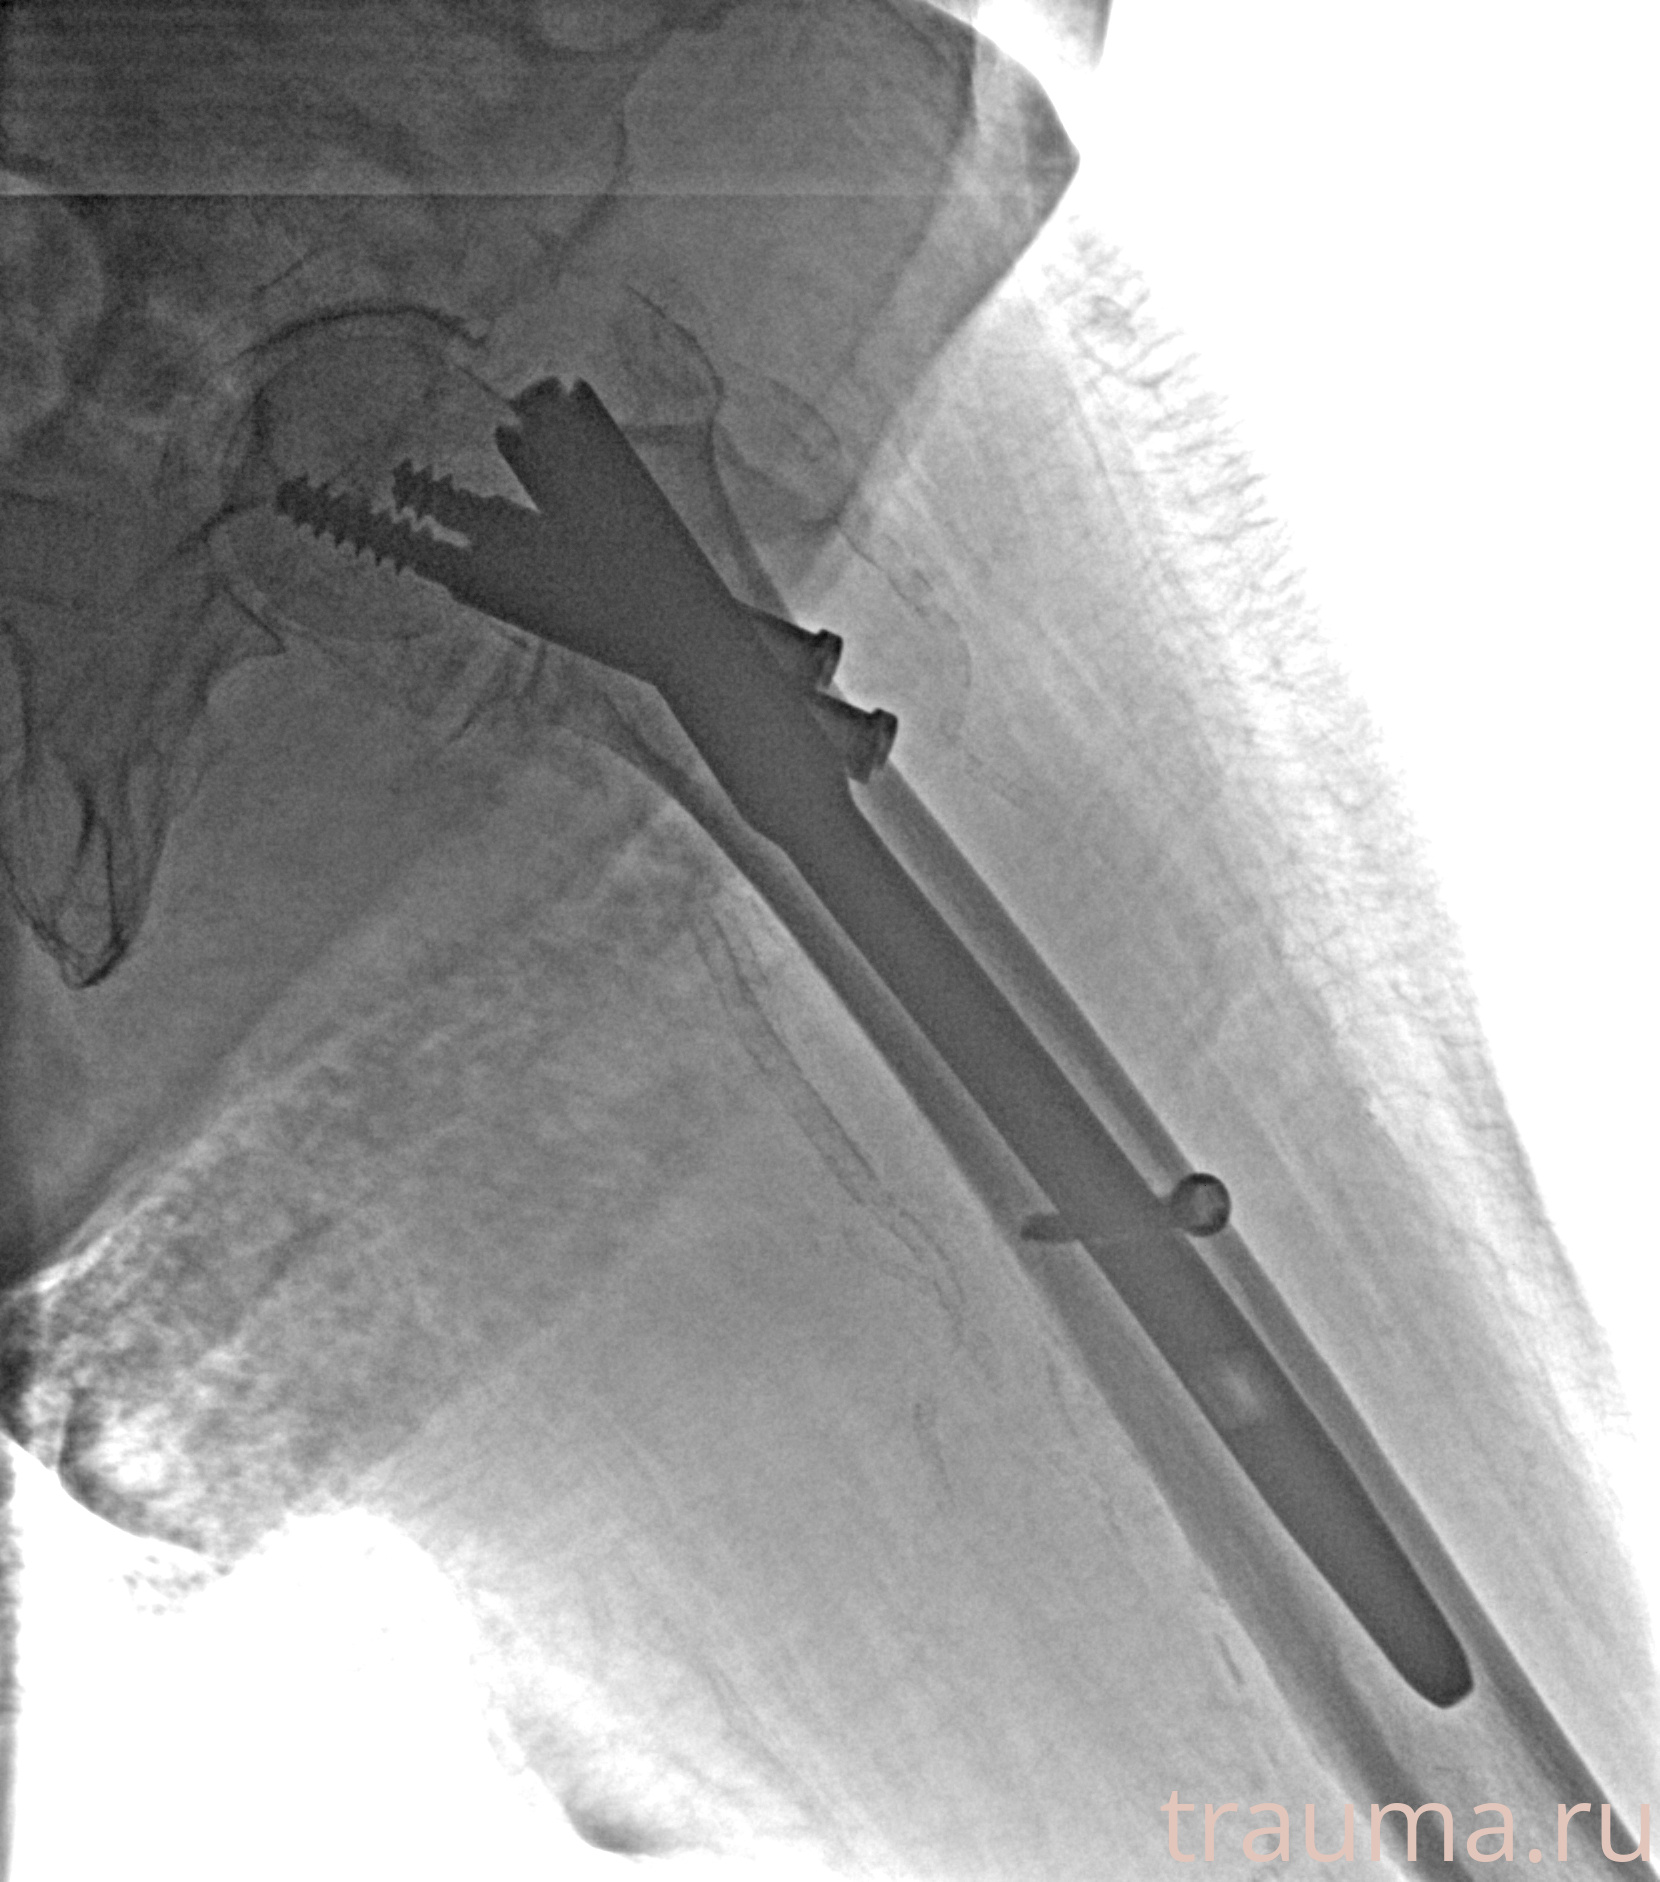

Рентгенограммы

Рентген на дому: по вашему адресу приезжает врач-рентгенолог, травматолог-ортопед с мобильным рентгеновским аппаратом, проводит диагностику травмы или заболевания, делает необходимые рентгенограммы, дает рекомендации по дальнейшему лечению. Получить качественные снимки в домашних условиях возможно благодаря уникальной методике, разработанной МосРентген Центром для института  Склифосовского

при переломе шейки бедра и пневмонии от компании МосРентген Центр - партнера Института имени Склифосовского